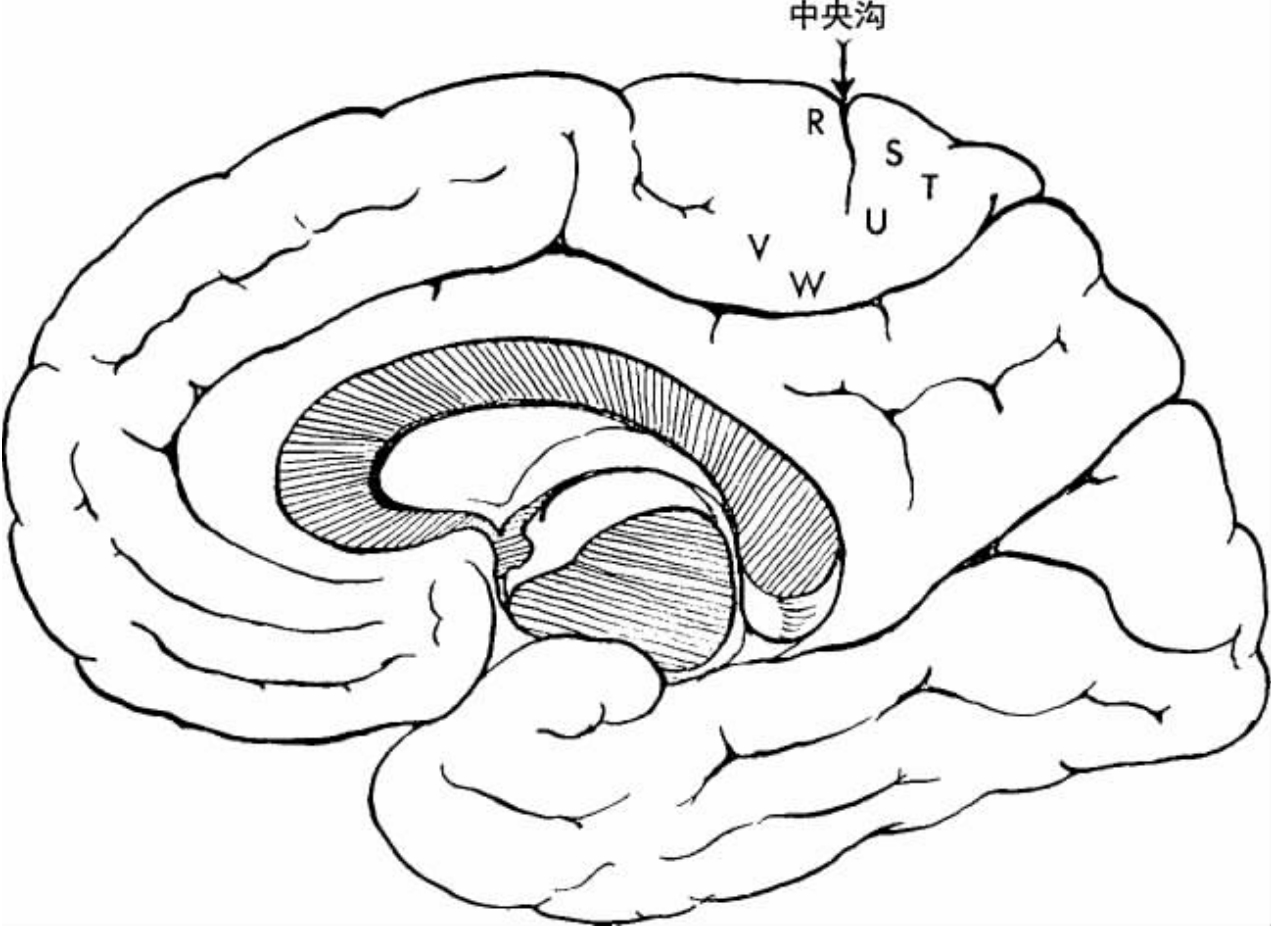

病例16 P.B.(麻木感,手、脚和腿的运动抑制。行左侧开颅术。局灶性皮质癫痫。颞叶前端切除)

患者是一位聪明的男士,也是一位理想的报告人。患者出现先兆,他觉得周围变得愚蠢而荒唐。他的左颞叶出现放电。行左侧开颅术。脑部的图像如图4-23和4-24所示。中央沟的后边界由1、2、3、4来显示,而11、17、12、15显示前方边界。在外侧裂上的点14之下可见增厚的蛛网膜白色条纹。